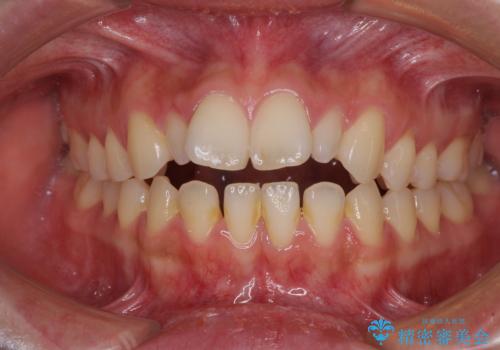

飛び出した前歯 インビザラインを用いた抜歯矯正治療

- 前方に飛び出した前歯を気にして来院された患者様です。

上下前歯同士の距離が離れているため、上顎左右第一小臼歯2本を抜歯することで前突を改善することとしました。

しかしながら、左右ともに側切歯が矮小歯であるため、矯正治療で矮小歯前後にスペースを作り、矯正治療後にオールセラミッククラウンにて補綴治療を行うこととしました。